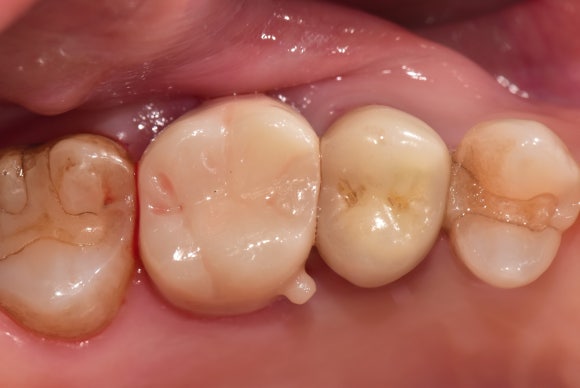

20250830

치아 가운데에 동그랗고 불투명한 것이 보입니다.

포스트의 단면입니다.

흰색은 레진입니다.

뿌리 위에 레진을 올리고, 이를 유지하기 위해 포스트를 삽입했다고 이해하시면 됩니다.

20251001

마무리는 언제나 튼튼한 크라운입니다.